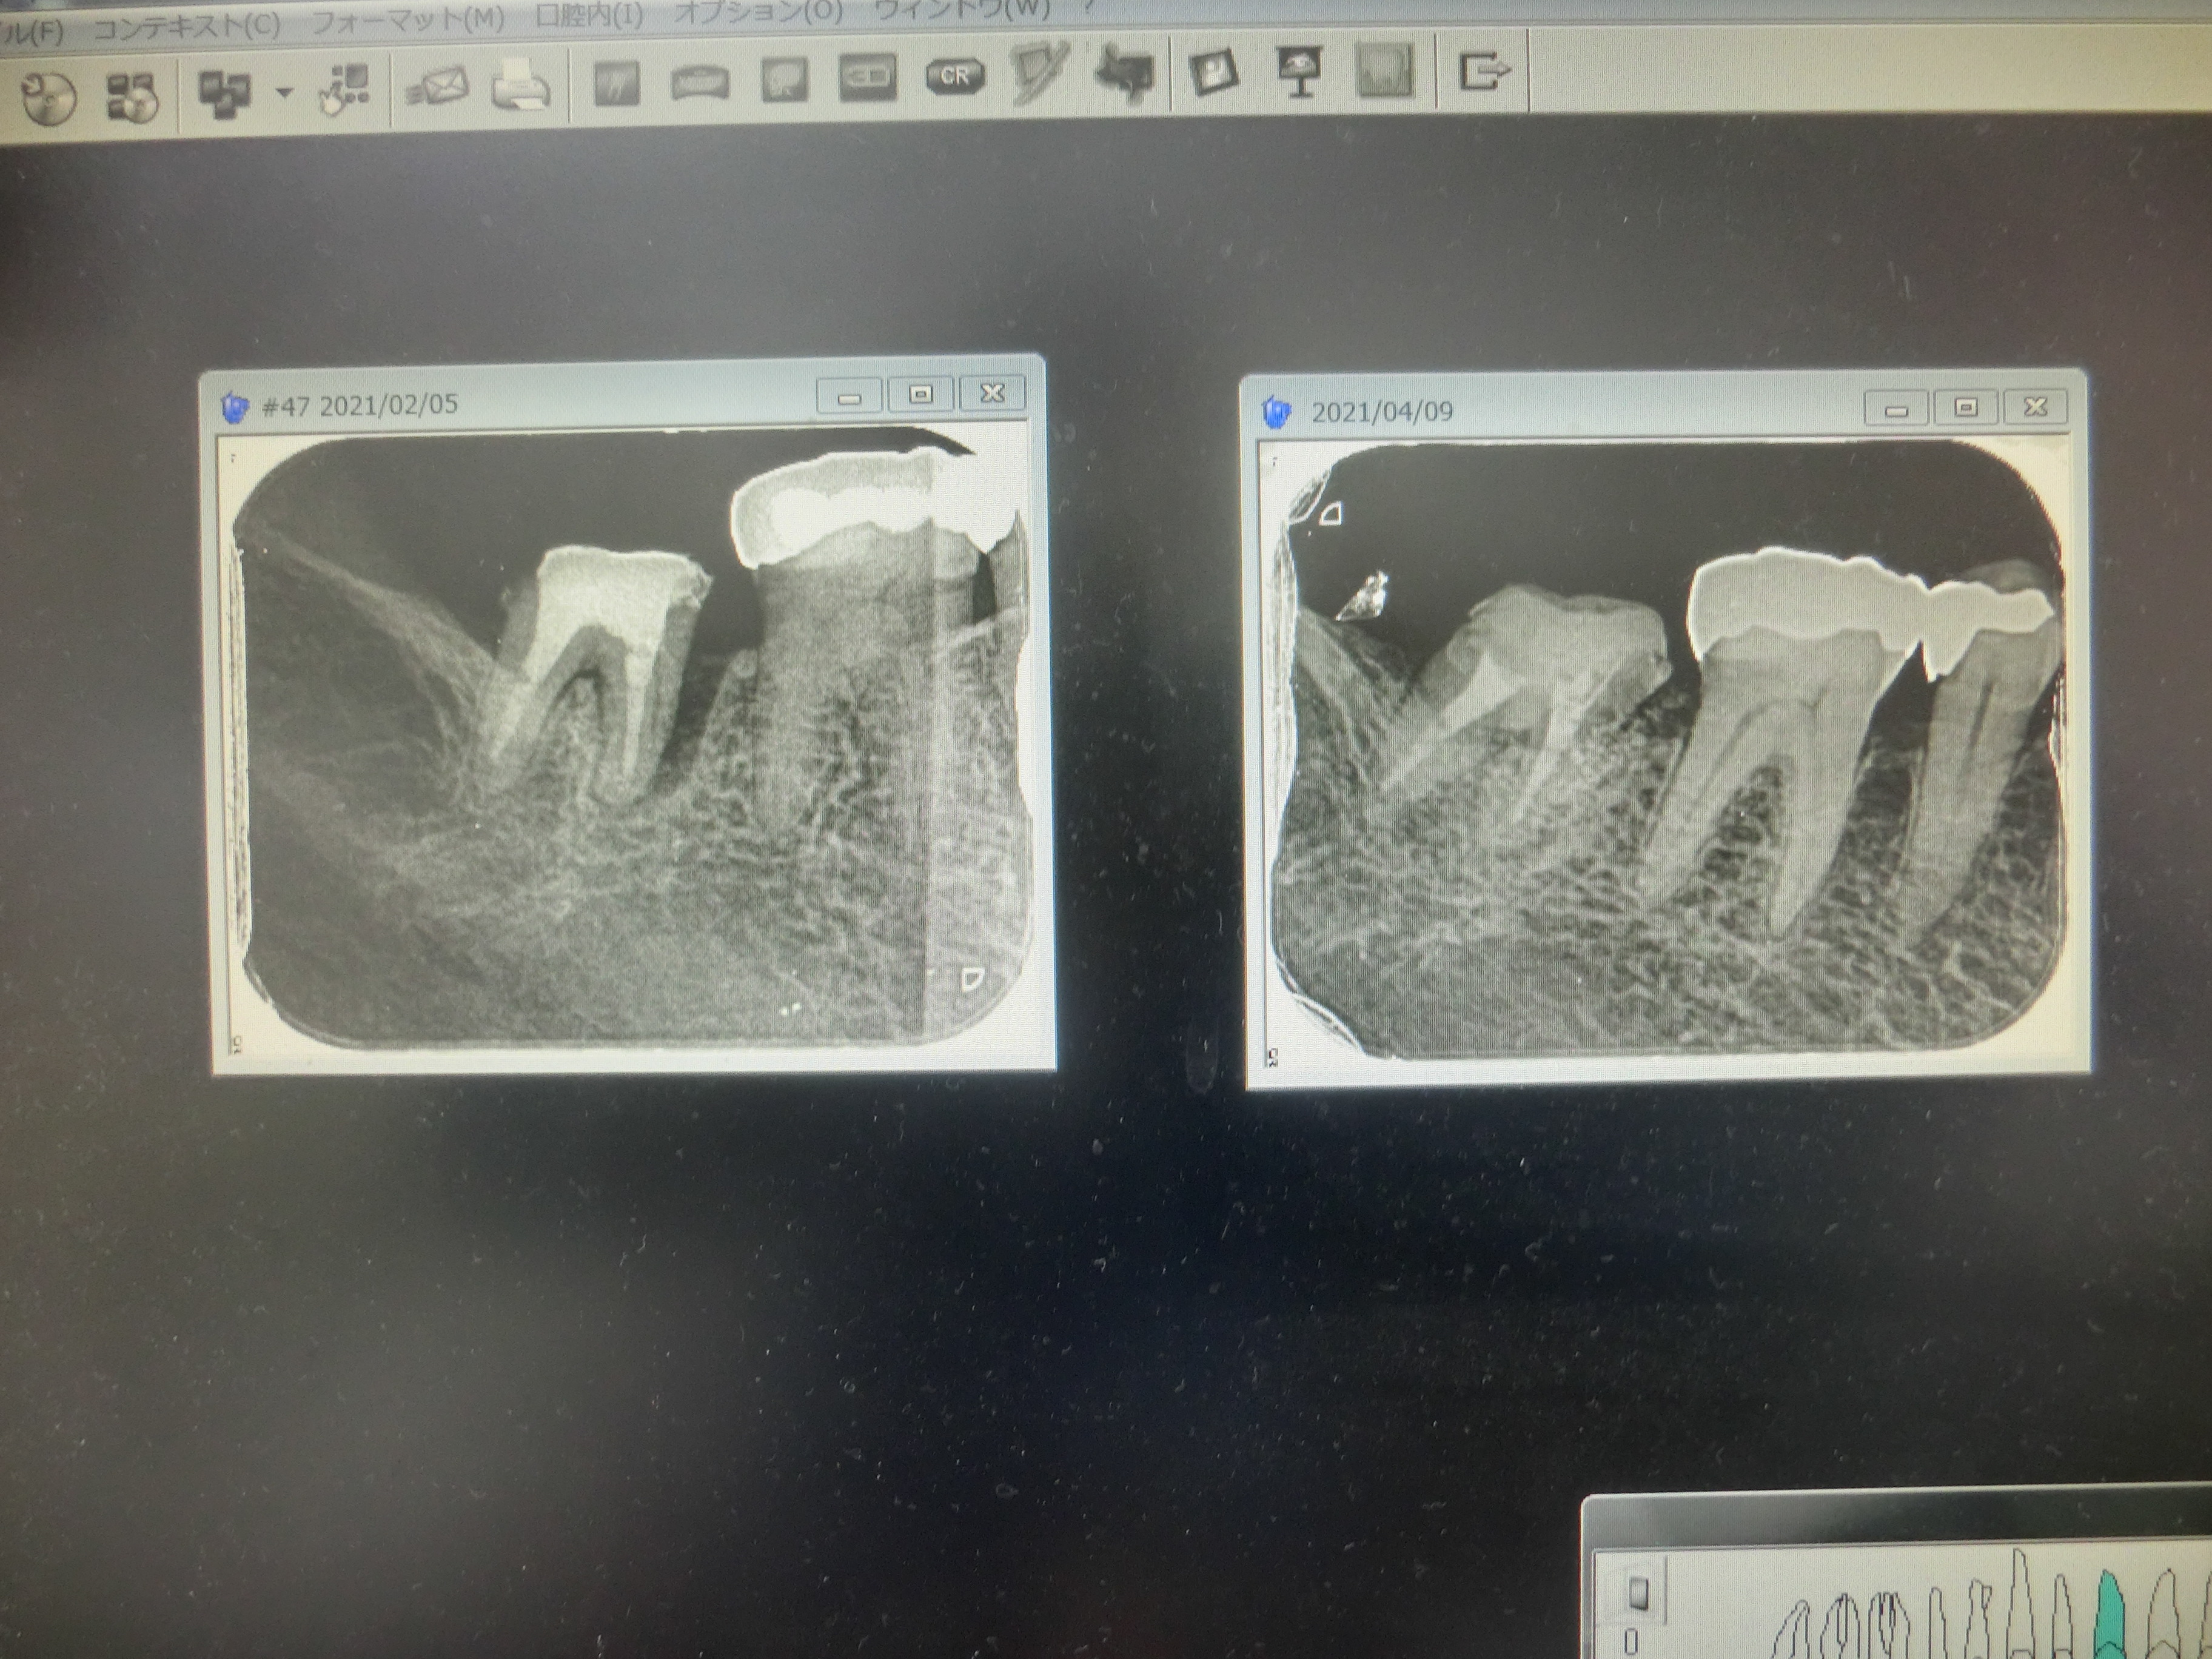

以下は直近の患者様の治療術前と術後の写真です。

下顎の第2大臼歯ですが、左側のレントゲン写真で

歯の根を支えている骨が溶けています。

そこで、基本的な歯周病治療後、不良な歯肉を除去し、

人工の骨を満たす手術をしました。

右は3ヶ月後のレントゲン写真です。

しっかり骨ができていて歯の動揺もなくなりました。

この第2大臼歯の治療はすべて保険診療の範囲内でおこなっています。

保険診療でここまで歯周病が治ります。